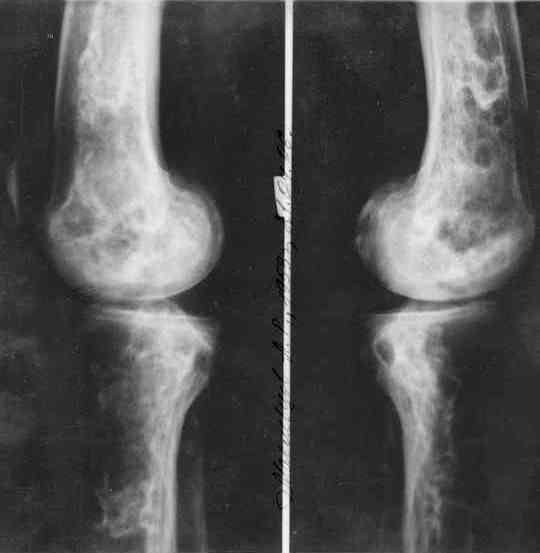

Мужчина, 53 года, жалуется на постоянные ноющие боли в костях голеней, усиливающиеся после ходьбы, боли в коленных суставах. Считает себя больным с 1987 г., когда впервые появились боли в коленных суставах. В 1990 г. выставлен д-з: вторичный ДОА коленных суставов, фиброзная дисплазия костей. После проведенного лечения (НПВП, радоновые ванны, курс введения кислорода в коленные суставы) в течение 5 лет ремиссия. С 1995 г. ежегодные обострения весной и осенью, проявляющиеся болями в коленных суставах, явлениями синовита. Проводилось лечение НПВП, физиопроцедуры, внутрисуставное введение дипроспана с положительным эффектом. С 2004 г. - эффекта от проводимой терапии нет. В 2006 г. впервые по рентгеновским снимкам выставлен д-з: болезнь Альберса-Шенберга. Деформирующий гонартроз справа 2 ст., слева 3 ст. С 2006 г. ездит на лечение в Китай, где проводится лечение радоновыми грязями, массаж с положительным эффектом. Объективно: коленные суставы деформированы, при пальпации б/болезненные. Движения в полном объеме. При ходьбе хромает. Диагноз: болезнь Алберс-Шонберга. Деформирующий гонартроз справа 2 ст., слева 3 ст.Хотелось бы уточнить диагноз и определить тактику дальнейшего лечения. Заранее спасибо.

Представленные Вами данные о пациенте 57 дет с болезнью Альбертс-Шенберга чрезвычайно интересны, но диагноз вызывает большие сомнения. Для мраморной болезни характерно прееобладание склероза, а на представленных рентгенограммах преобладает симметричная дезорганизация архитектоники губчатой кости в эпиметафизарной зоне дистальных отделов бедер и голеней.

Мне кажется, представленные рентгенограммы скорее соответствуют варианту фиброзной дисплазии который был описан М. Campanacci (1976) или

обызвествляющей фиброме H.E.Schlitter (1958).

Уважаемый Константин Иванович! Полностью согласен с проф. Михайловым, данный случай не похож на мраморную болезнь, при которой имеется резкое, строго симметричное и генерализованное уплотнение костной ткани (остеопетроз), и кость оказывается построенной преимущественно из гомогенного компактного костного вещества. Для примера привожу случай из архива нашего института (бедренные, плечевые кости и таз, рис 1,2,3)

Изменения структуры костей у Вашего пациента больше похожи на полиоссальную форму фиброзной дисплазии или болезнь Педжета, возможены также инфаркты костного мозга б.берцовых костей. К сожалению, качество снимка не очень хорошее, непонятно, сохранен ли кортикальный слой б.берцовых костей по передней поверхности.